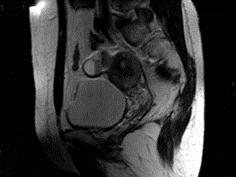

问题 女性,46岁,无任何不适,体检扪及盆腔包块,行MRI检查,如图所示,最佳答案是 ( )

选项 A、卵巢粘液囊腺瘤 B、卵巢结核 C、卵巢皮样囊肿 D、卵巢粘液癌 E、卵巢囊肿

答案 E